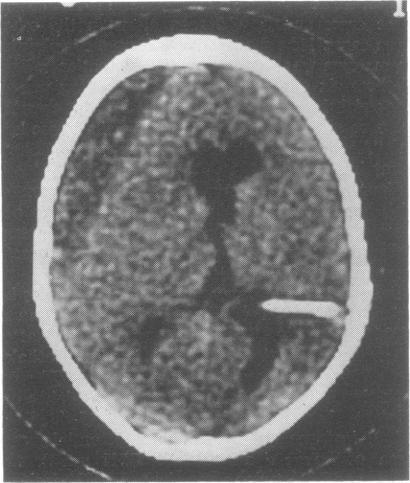

Of 30 consecutive children with hydrocephalus treated by shunt implant, six developed subdural haematoma. Four of them presented with a malfunctioning shunt, and the diagnoses in all six cases were made by CT scan.

在连续接受分流植入治疗的30例脑积水患儿中,6例发生了硬膜下血肿。其中4例出现分流装置故障,所有6例的诊断均通过CT扫描做出。